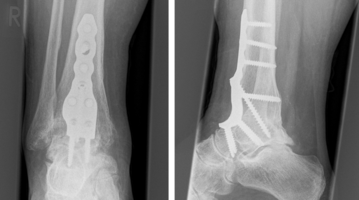

In ausgeprägten Fällen kann eine Korrektur im Mittelfuß-Schaftbereich oder sogar eine Versteifung des Verbindungsgelenks zwischen Fußwurzel und Mittelfuß erforderlich werden. Das Ergebnis der Korrektur wird durch spezielle Metallimplantate gesichert. Diese sind dank moderner Entwicklungsmethoden sehr dünn, sodass keine Weichteilirritationen entstehen. Gleichzeitig wird die erforderliche Stabilität gewährleistet.

Behandlung eines einfachen Falls des Hallux valgus | Behandlung eines ausgeprägten Falls des Hallux valgus |